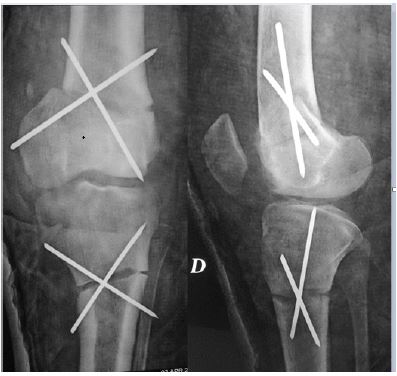

We performed a combined medial closing wedge osteotomy on the distal femur and the proximal tibia since the deformity interested both segments. Due to our experience with children, we decided to stabilise osteotomies with cross K-wires associating an above knee cast for two months (Figure 3).

Figure 3: Post-operative x-ray with immediate correction and kwire stabilization.